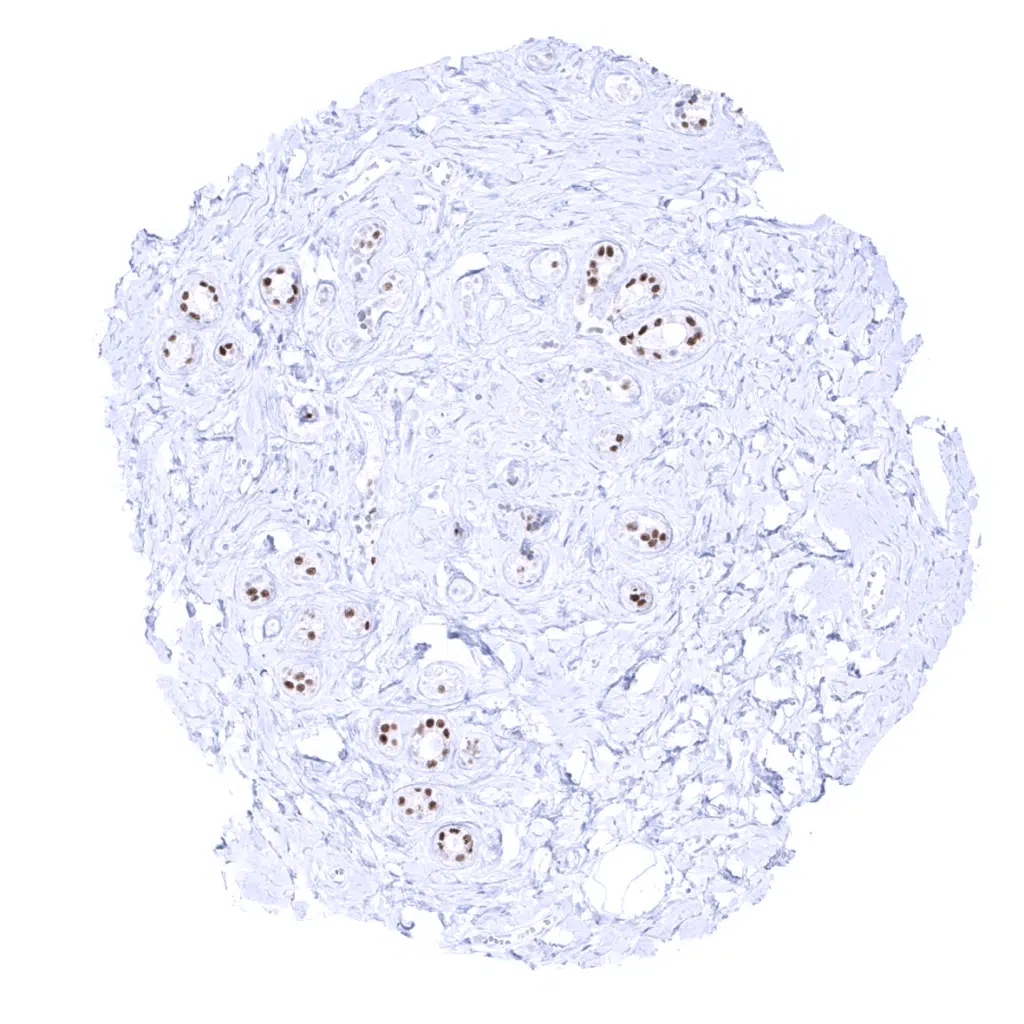

Kidney, cortex – A moderate to strong GATA3 positivity occurs in podocytes and in collecting ducts.

Kidney, medulla – A moderate to strong GATA3 positivity is seen in collecting ducts.